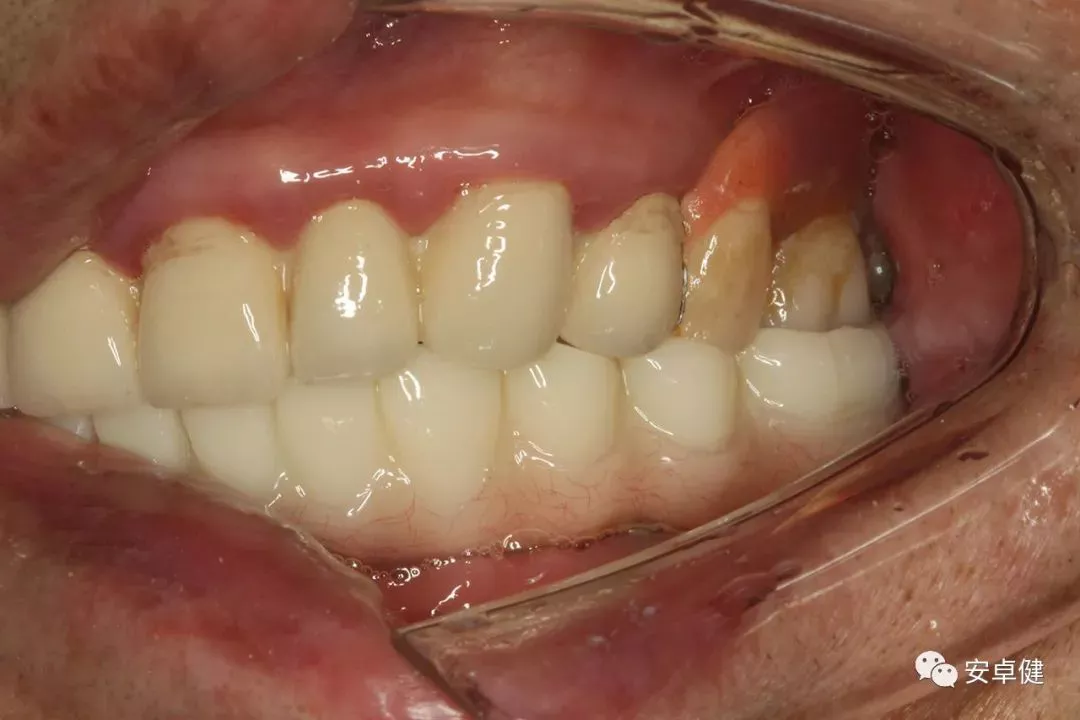

最终修复体侧面咬合照

• 修复体外形能够正确恢复面下1/3高度及侧貌;

• 患者可获得较为稳定的咬合关系,并满足其咀嚼功能的需求;

• 患者42、46部位牙龈退缩,缺乏足够的角化龈,为方便后期清洁维护,选择穿龈较高的龈上肩台;

• 口内观察,修复体边缘金属基台颜色暴露,但由于其处于下颌后牙非微笑暴露区,故对临床整体美观效果的影响在患者可接受范围内。